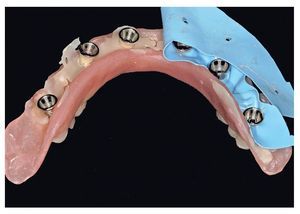

Fig. 69. Los implantes y las cofias provisionales para prótesis atornilladas colocados en el maxilar inferior.

Tras una fase de curación sin complicaciones, se esperaron otros dos meses antes de ajustar las prótesis provisionales a las condiciones ahora estables de la mucosa. Se rebasaron los espacios intermedios formados a causa de la detumescencia del tejido blando tras la intervención, a fin de reducir o incrementar el volumen del cuerpo de la prótesis conforme a las indicaciones funcionales, higiénicas, fonéticas y estéticas, así como teniendo permanentemente en cuenta la oclusión. Una vez concluida esta fase pueden tomarse las impresiones para la restauración definitiva (figs. 75 a 79). Para la restauración de puente planificada, se toman las impresiones a nivel del implante.

Fig. 76. La toma de impresión definitiva en el maxilar superior tiene lugar a la altura del hombro del implante.

Fig. 77. La toma de impresión definitiva en el maxilar inferior tiene lugar a la altura del hombro del implante.

Fig. 78. Vista detallada de la impresión del maxilar superior.

Fig. 79. Vista detallada de la impresión del maxilar inferior.